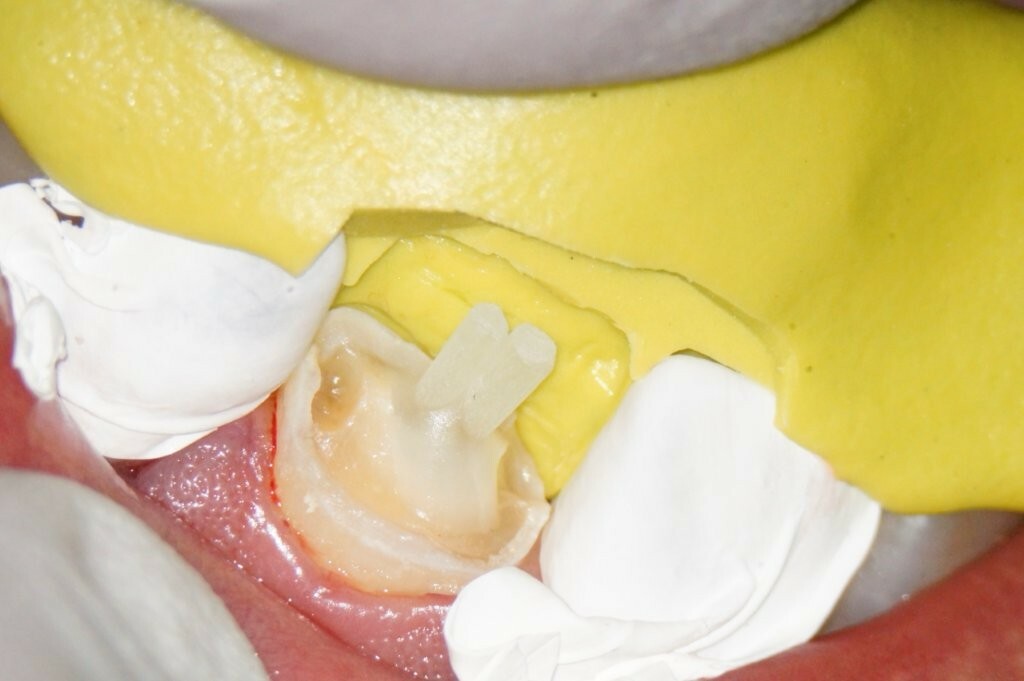

Das Zahnfragment hatte eine gute Passung auf den frakturierten Stumpf. So konnte im Vorfeld ein Silikonabdruck als Vorwall für den Kompositaufbau erstellt werden. Die endodontische Therapie sowie der Füllungsaufbau erfolgten ausschließlich unter dem hochauflösenden OP-Mikroskop (Zumax OMS2350). Die zu behandelnde Region wurde mit Ubistesin 1/200000 lokal betäubt. Anschließend wurde von 11 bis 22 ein Kofferdam angebracht. Der Zahn wurde mit einem konischen Diamanten trepaniert, die Trepanationsöffnung mit Gates-Glidden-Bohrern erweitert. Die Aufbereitung erfolgte mit dem Reciproc Blue System bis zur Größe 50.05.